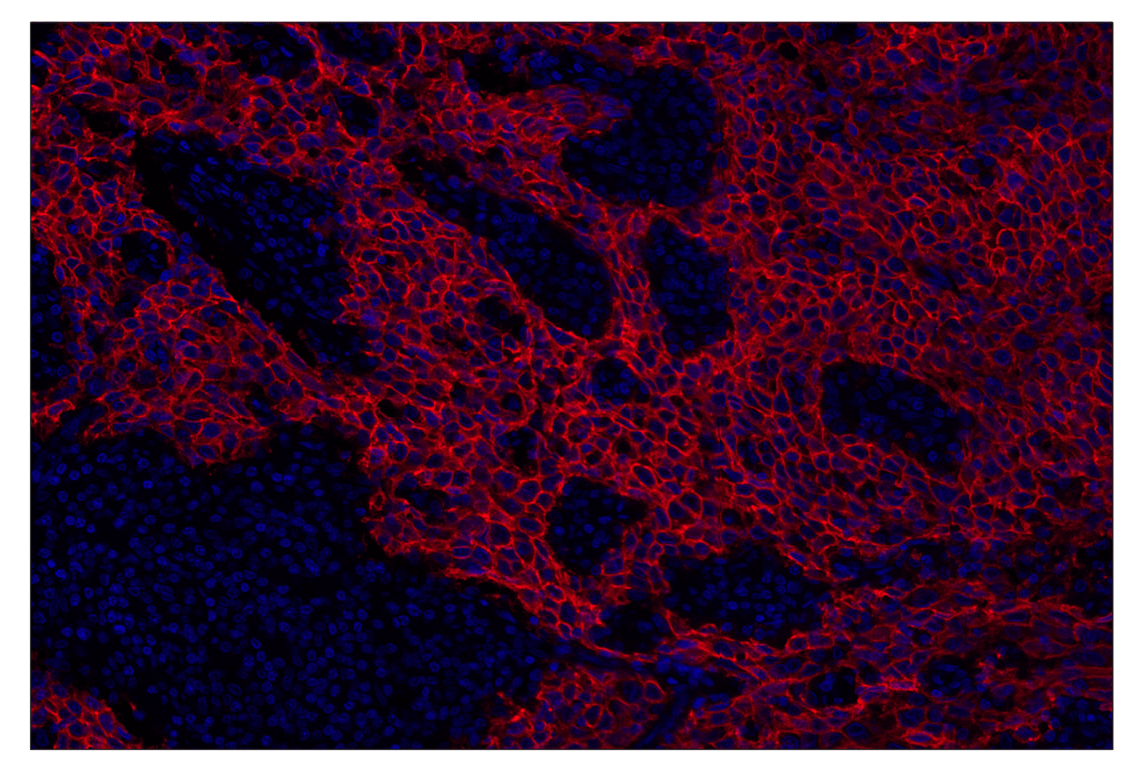

SignalStar™ multiplex immunohistochemical analysis of paraffin-embedded human squamous cell carcinoma of the cervix using TACSTD2/TROP2 (F4W4J) & CO-0150-647 SignalStar™ Oligo-Antibody Pair #94656 (red) and DAPI #4083 (blue). All fluorophores have been assigned a pseudocolor, as indicated.

Immunohistochemistry Image 3: TACSTD2/TROP2 (F4W4J) & CO-0150-488 SignalStar<sup>™</sup> Oligo-Antibody Pair